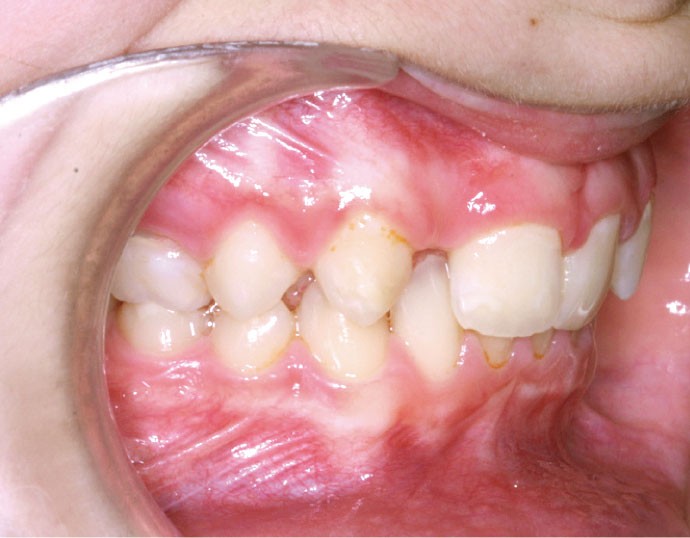

Ludivine T. âgée de 12 ans et demi présente une agénésie des deux incisives latérales maxillaires dans un contexte occlusal de classe II division 2 (fig. 1 à 3).

Les vues endo-buccales (fig. 2) montrent la classe II division 2 occlusale associée à une forte supraclusion incisive et l’évolution spontanée de 13 et 23 pratiquement en place de 12 et 22. Il persiste cependant un diastème disgracieux entre 13 et 11.